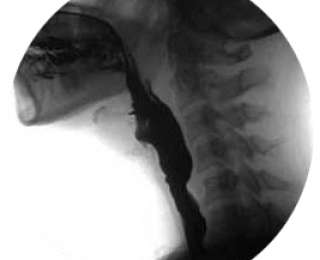

Տեսեք, թե ինչ է կատարվում ձեր մաշկի տակ:

Բերան

Կոկորդ